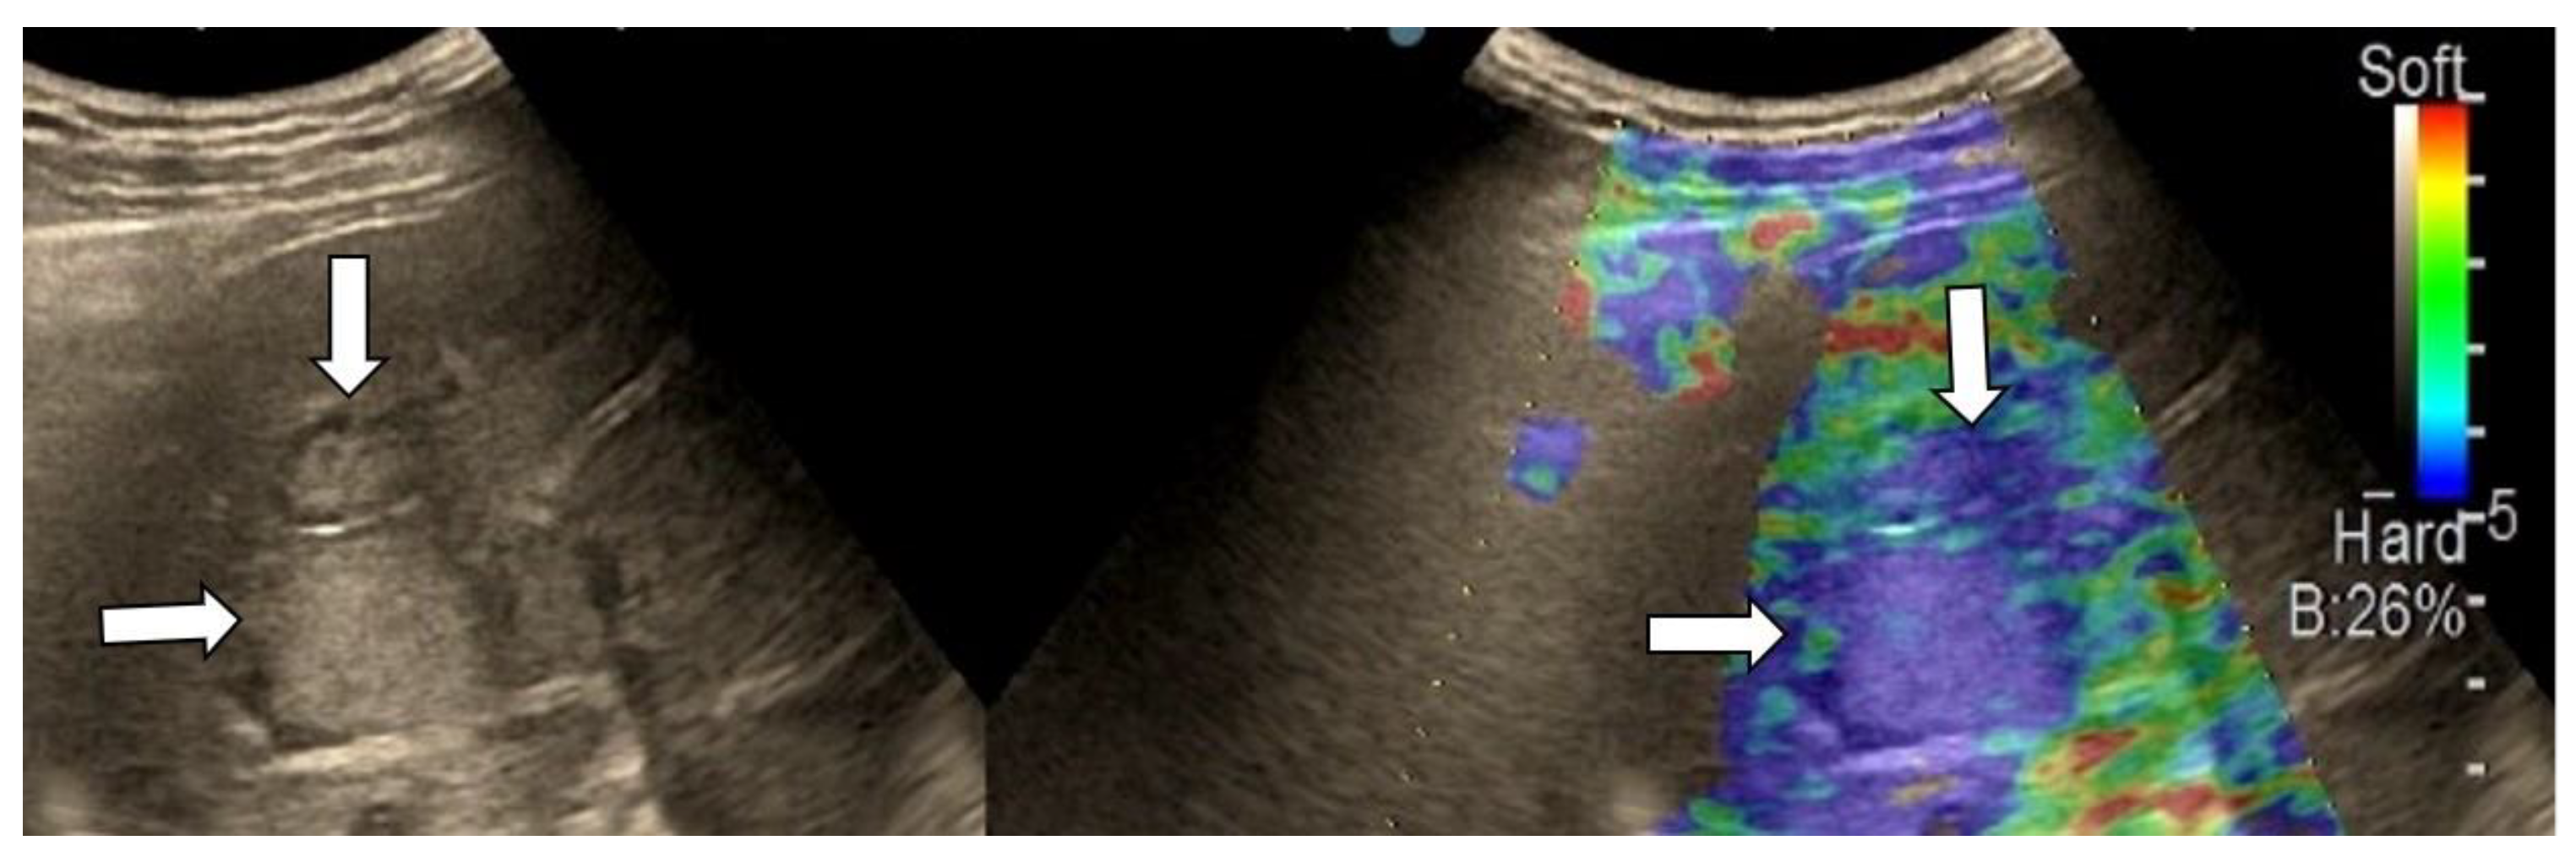

3.4. Real-Time Tissue Elastography

| Elasticity Type | Color Code |

|---|---|

| Type “a” | Homogenously green |

| Type “b” | Mosaic pattern with dominant green areas |

| Type “c” | Mosaic pattern with dominant blue areas |

| Type “d” | Homogenously light blue |

| Type “e” | Homogenously dark blue |

| RTE | Liver Adenoma | HMG | FNH | Complicated Liver Cyst | HCC | iCCA | Liver Metastases | Liver Lymphoma |

|---|---|---|---|---|---|---|---|---|

| Type “a” | 3 | 1 | ||||||

| Type “b” | 1 | 1 | 10 | 3 | 1 | |||

| Type “c” | 1 | 24 | 3 | 6 | ||||

| Type “d” | 1 | |||||||

| Type “e” | 5 | 3 | 1 |